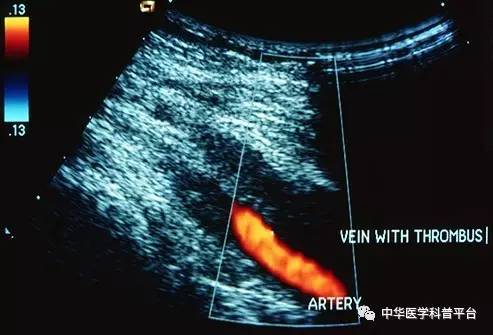

诊断:医生会对你进行查体以确定是否有DVT的症状,并询问你可以增加患这种疾病的机会的事情,如你的病史和你正在服用的药物,以及你的家族史等。超声波是最常见的明确诊断方法,其使用声波来“看到”血流并显示凝块,当然可能还需要其他检查,例如称为d-二聚体的血液检查等。